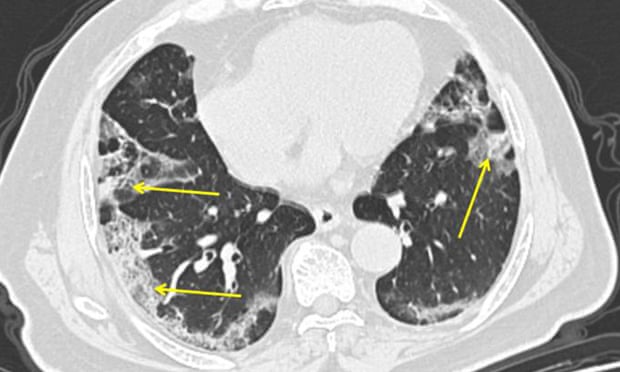

Microbiologists from the University of Hong Kong have carried out groundbreaking research comparing how the new coronavirus and the Sars virus act in human lungs, and come to the conclusion that the new virus will disrupt life in the the city for months, RTHK reports.

The team, led by Yuen Kwok-yung and Jasper Chan, obtained samples of living lung tissue from six donors, which they then infected with the two viruses. They said the new coronavirus was able to replicate fast without triggering a strong immune response.

“We have seen that [Covid-19] acts like a ninja, it can evade the detection of the body without triggering a very strong reaction, like inflammation, in the body, so it can replicate to a very high level,” Chan said.